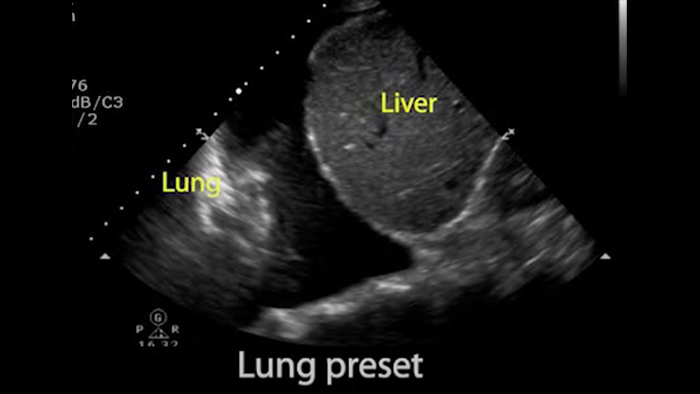

Utilice Lumify para la evaluación de las vías respiratorias y pulmonares

Las soluciones Lumify POCUS pueden ayudarle a detectar el tubo endotraqueal dentro de la tráquea, ayudar en los procedimientos de cricotirotomía emergentes, en el diagnóstico de derrame pleural y enfermedades alveolares intersticiales.

Transductor de disposición en fase de banda ancha Lumify S4-1

• Rango extendido de frecuencias de operación de 4 a 1 MHz • 2D, Doppler a color, Modalidad M, XRES avanzado e imágenes armónicas multivariables • Imagenología de alta resolución para aplicaciones abdominales y cardíacas: optimizaciones de preajustes de imágenes cardíacas, gineco-obstétricas, pulmonares, abdominales y FAST.

Ultrasonido cardíaco en el punto de atención prehospitalario: embolia pulmonar

Conceptos básicos del ultrasonido pulmonar